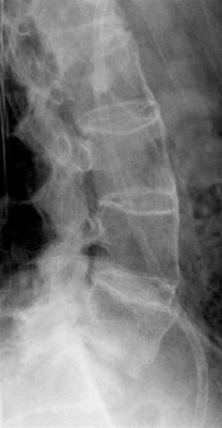

• Tegn på røntgenologisk betændelse i bækkenet

• Disse optræder sent i forløbet

• MR-skanning kan vise tidligere stadier af sygdommen